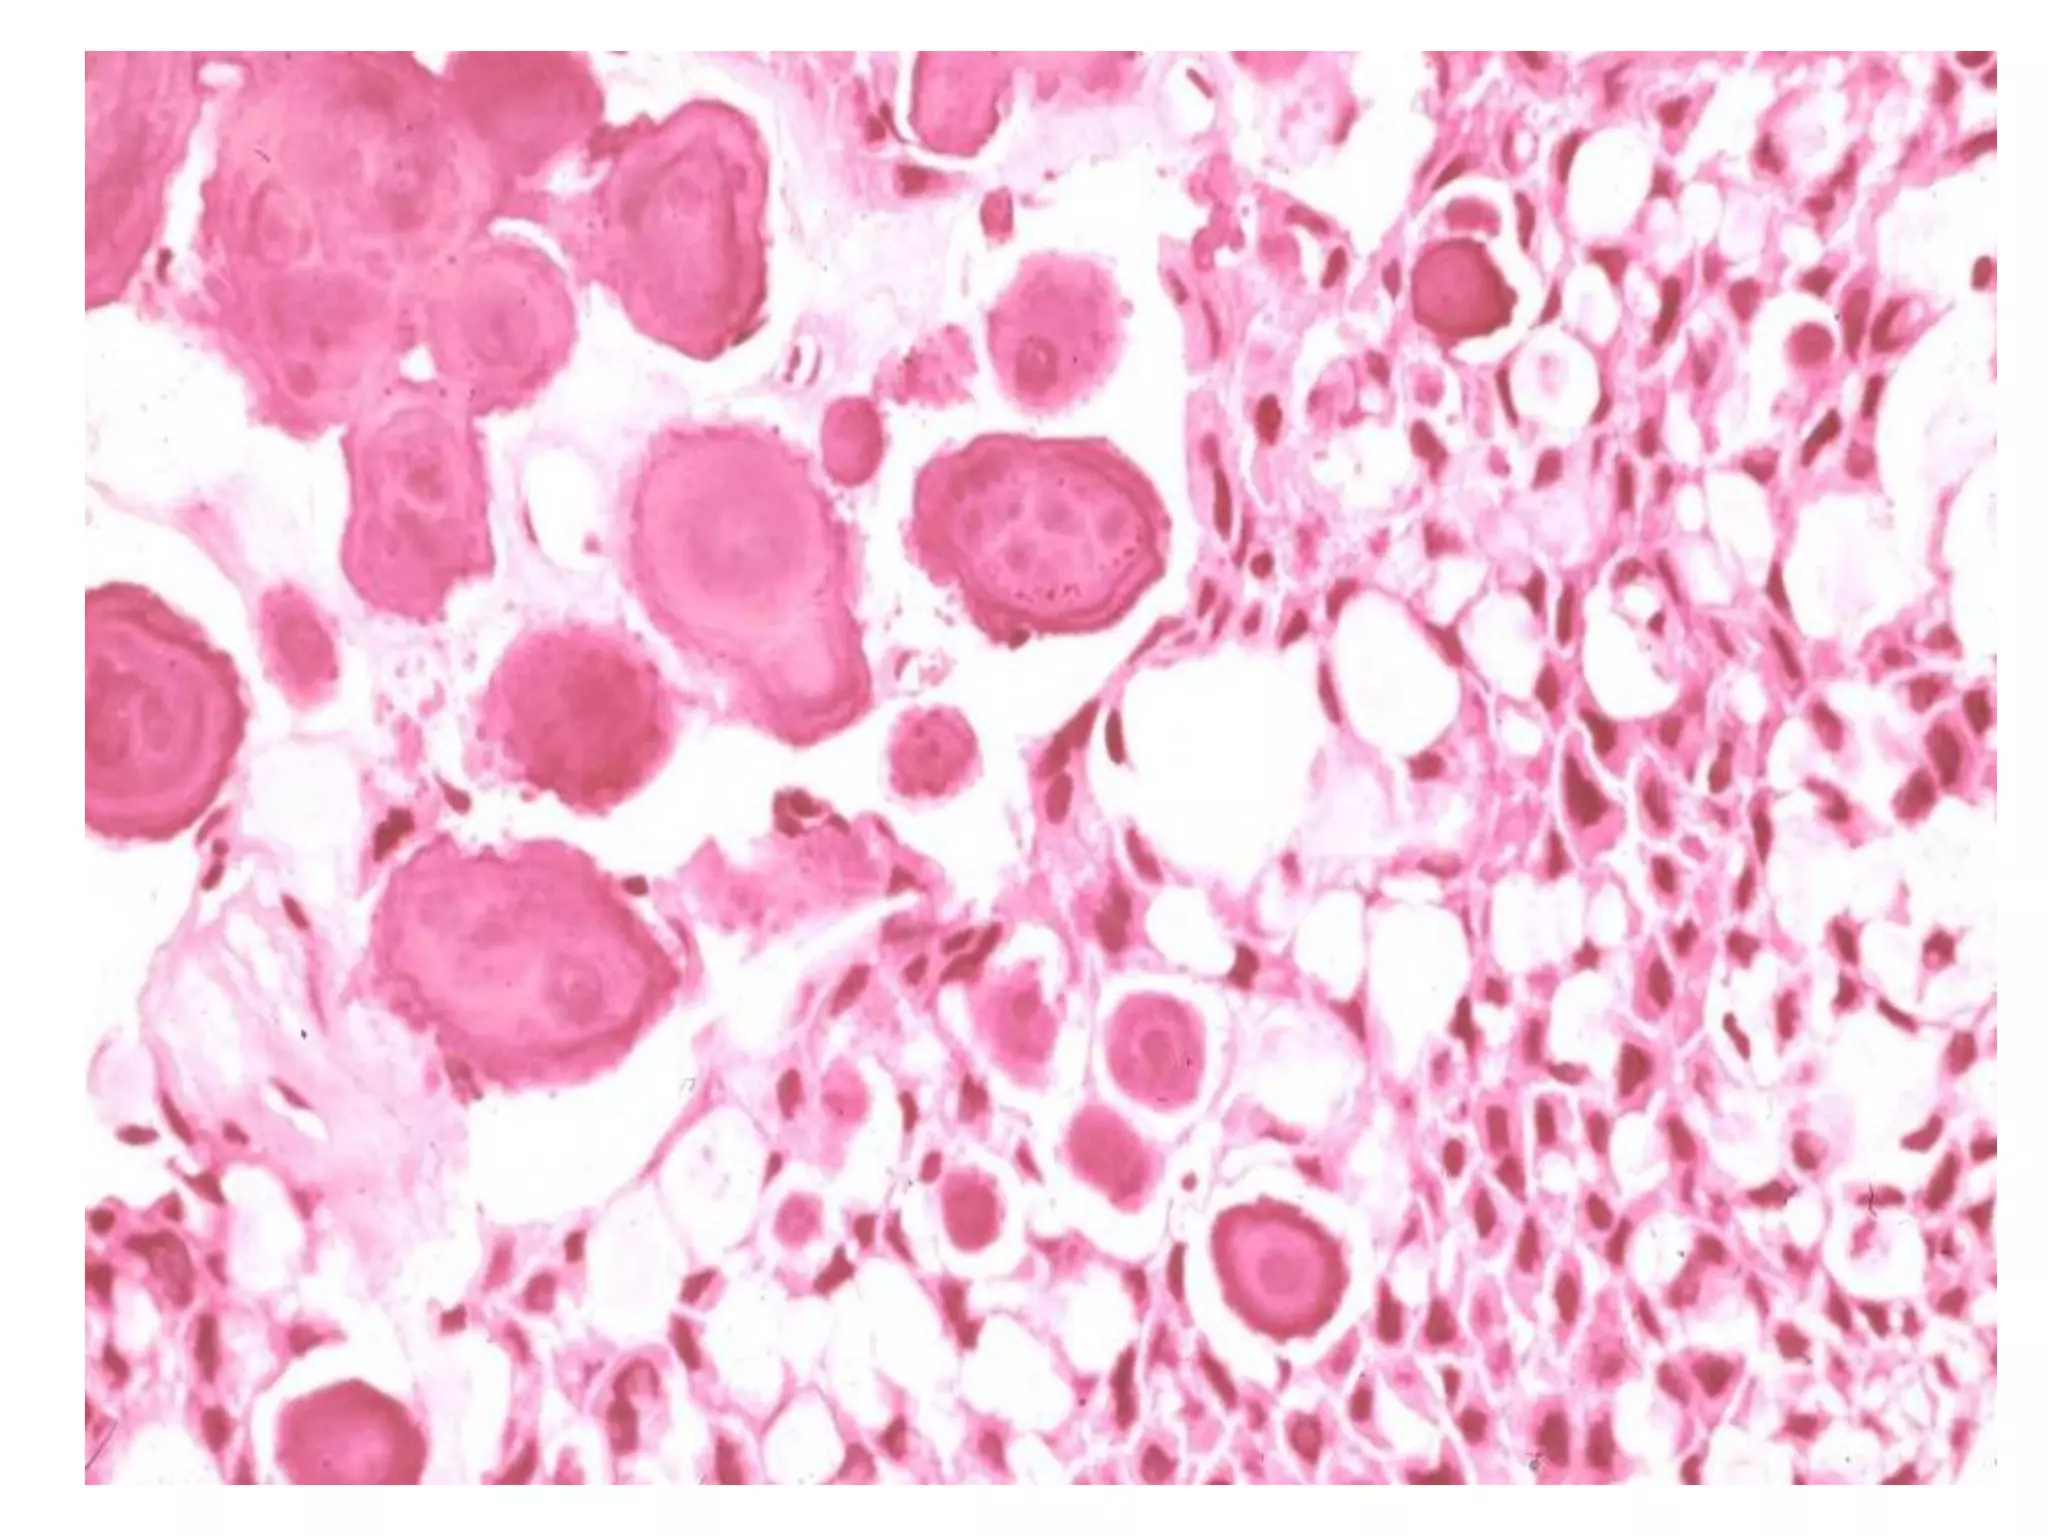

 U men ñaëc daïng teá baøo haït (granular cell

type) coù söï bieán ñoåi moät nhoùm caùc teá baøo

bieåu moâ thaønh teá baøo haït, söï bieán ñoåi naøy thì

chöa roõ. Loaïi naøy thöôøng gaëp ôû ngöôøi treû vaø

treân laâm saøng cho thaáy daáu hieäu xaâm laán.

granular cell type